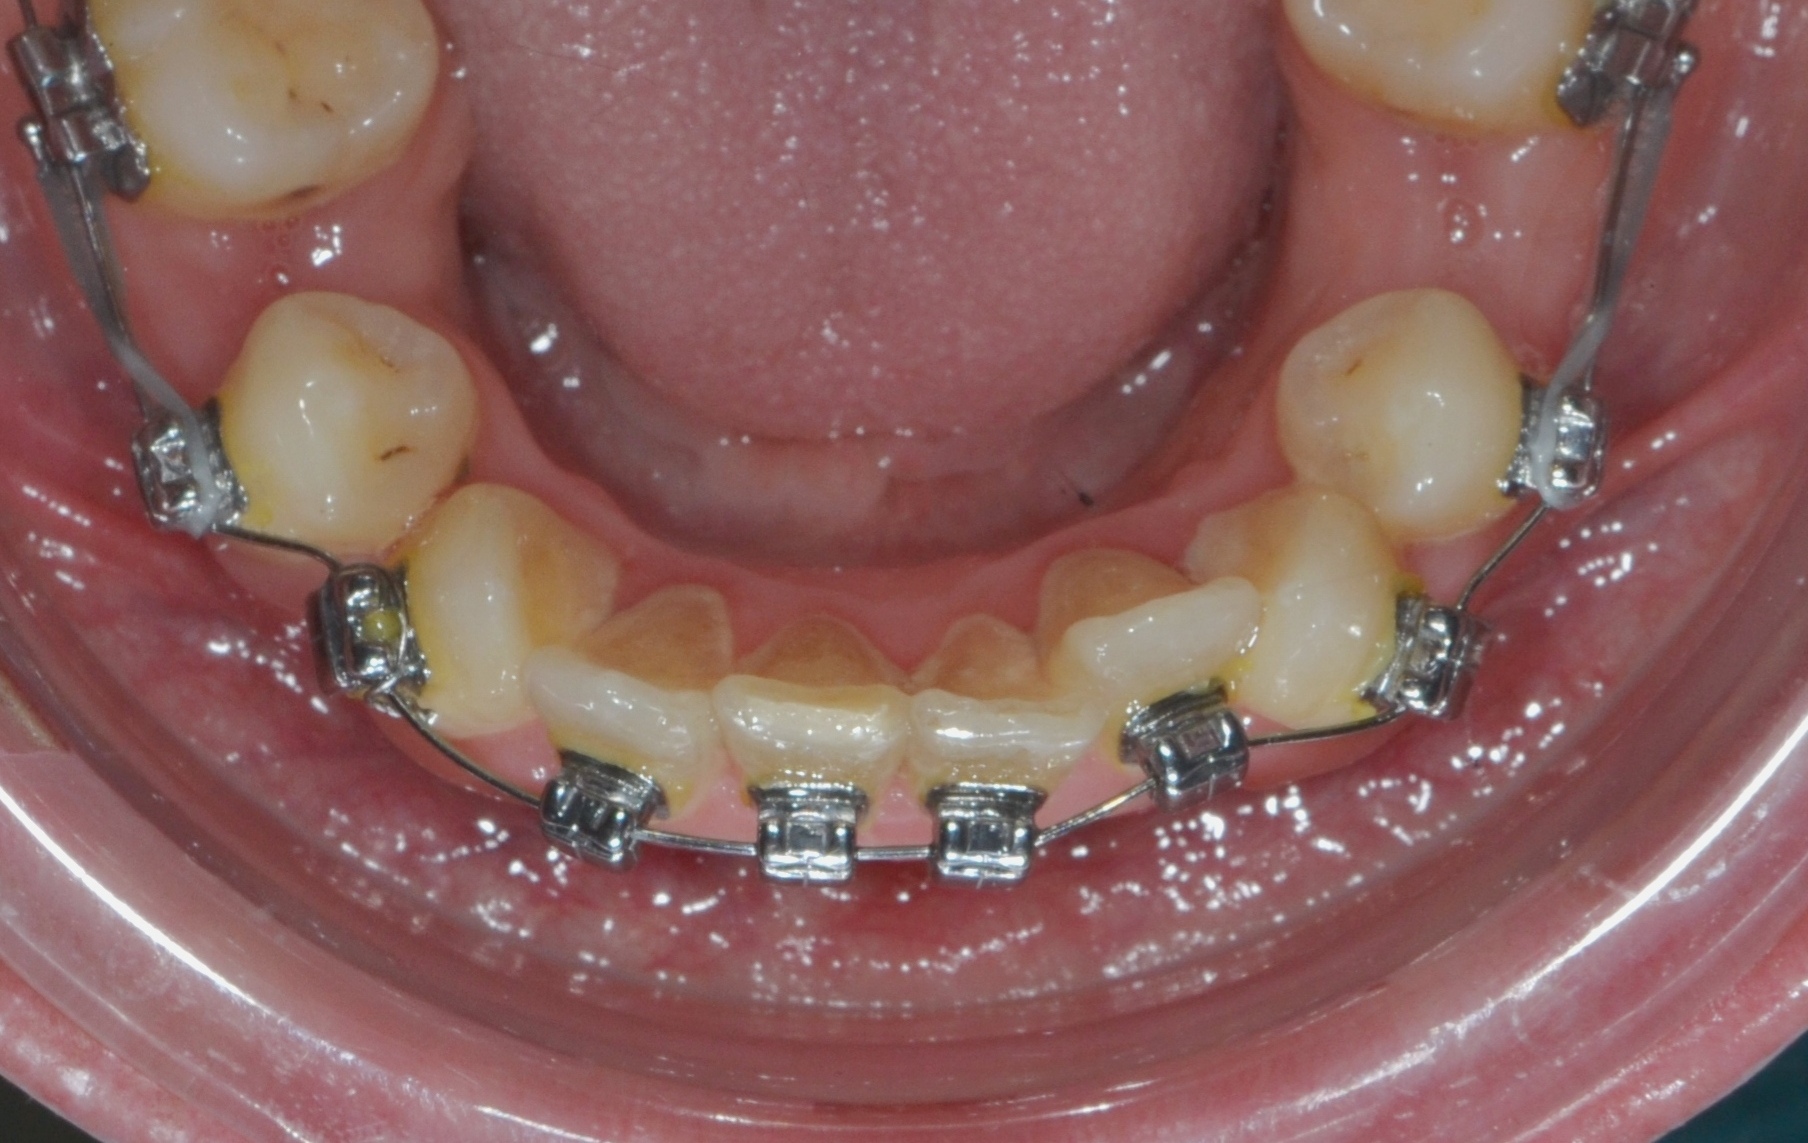

До фиксации

Декабрь 2024 г.

2

1.5 месяца

Частичная ретракция премоляров и клыков 1.5 мм